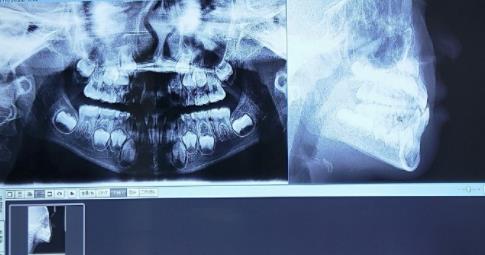

替牙期牙齒拍片